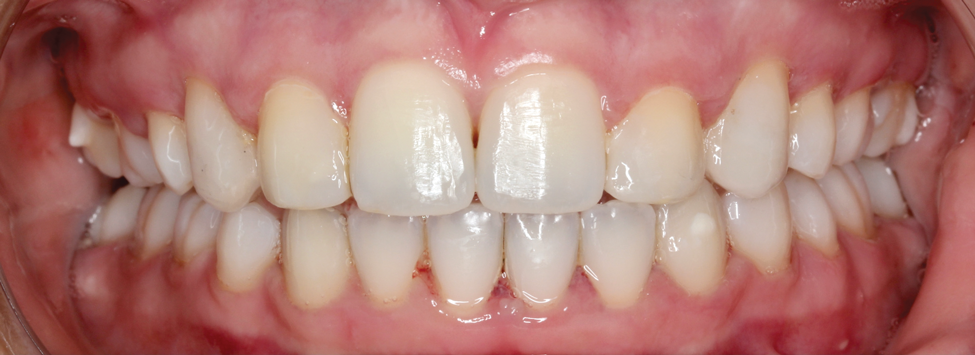

Fig 1. Patient was missing teeth Nos. 7 and 10 (Fig 1). Canine substitution was the treatment used to replace these missing teeth (Fig 2).

Fig 2. Patient was missing teeth Nos. 7 and 10 (Fig 1). Canine substitution was the treatment used to replace these missing teeth (Fig 2).

Canine substitution can be an excellent alternative for the replacement of the missing maxillary lateral incisor (Figure 1 and Figure 2). This treatment option can be particularly effective if the canine has a flat facial surface, is not too wide mesiodistally, and has a color similar to the contralateral lateral incisor. Patients with missing lateral incisors who present with maxillary dentoalveolar protrusion and/or an Angle class II molar relationship and minimal crowding in the mandibular arch are considered excellent candidates for canine substitution.7